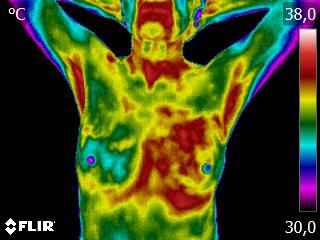

Ni radiation, ni compression, sans douleur et sans risque pour la santé, sans aucun contact direct, l’examen thermographique des seins consiste simplement à mesurer et analyser les variations et l’intensité de la chaleur (ou énergie thermique) émise par les différentes parties de vos seins. Clairement plus agréable que le calvaire de la mammographie !

Le principe est simple: dans les tissus pré-cancéreux et autour d’une inflammation en développement, les vaisseaux sanguins ont une activité plus élevée que dans un sein normal. Cela produit une chaleur que nous allons mesurer avec une infime précision, à l’aide d’une caméra infrarouge à la pointe de la technologie moderne.

Chaque être, chaque corps est unique: vos seins le sont aussi. Lors d’un premier examen, nous comparons les deux seins et cherchons d’éventuelles asymétries. Nous établissons également une thermographie (cartographie) de vos seins, à laquelle nous pourrons comparer les images d’examens ultérieurs.